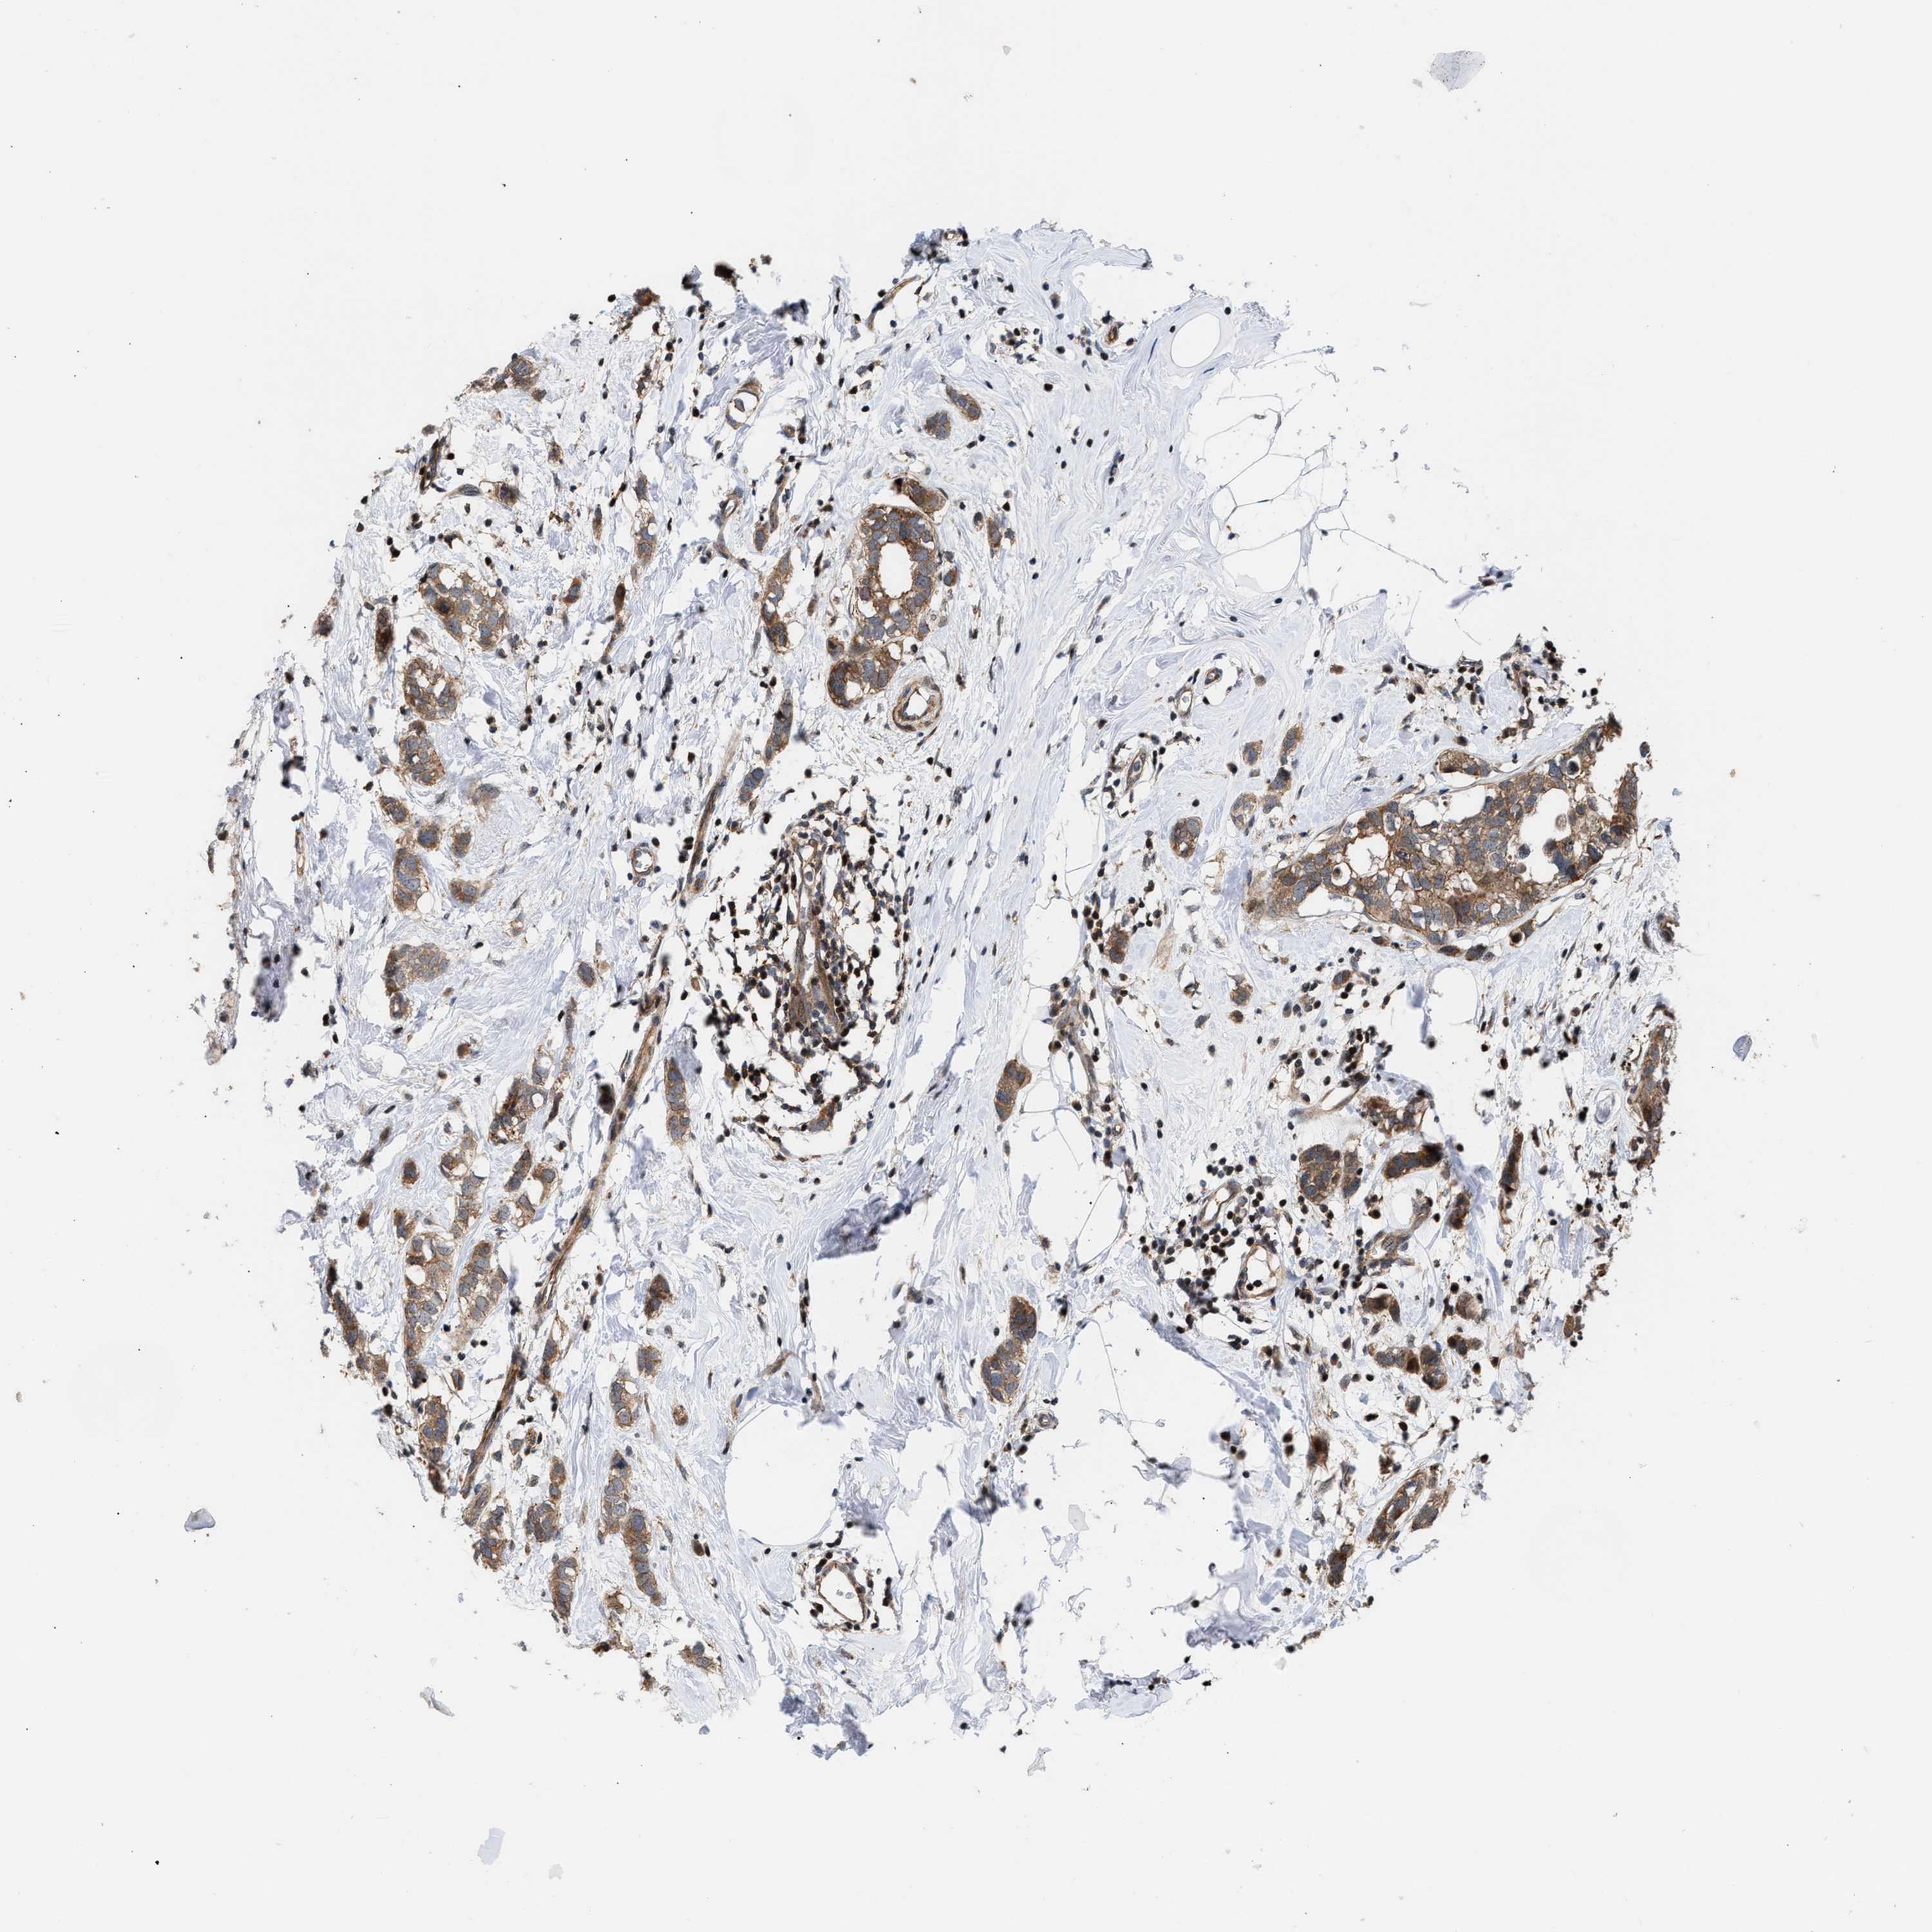

CANCER BREAST CANCER Show tissue menu

BRCA TCGA BRCA VALIDATION PROTEIN EXPRESSION